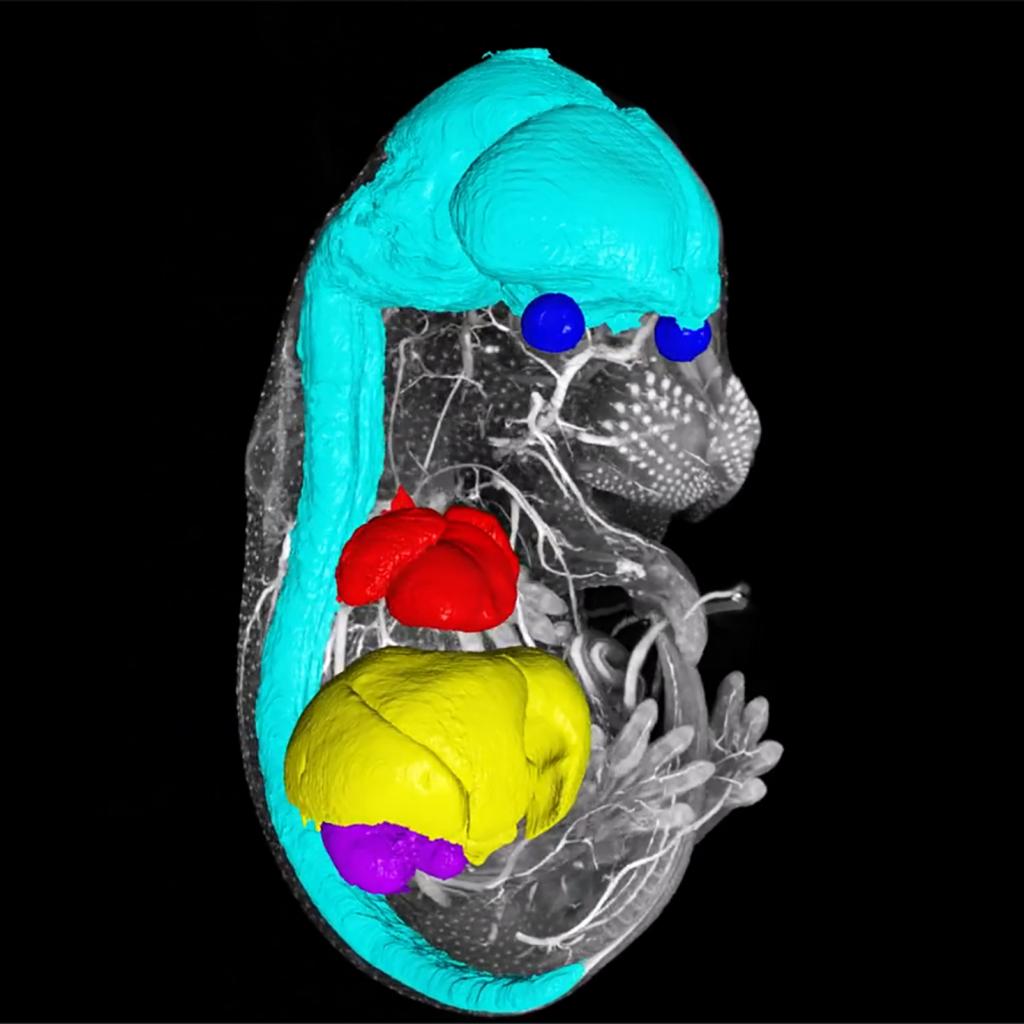

NEW!心臓色分け | 京都科学,

NEW!心臓色分け | 京都科学, ZEISS Versa:高度な3D X線顕微鏡(XRM),

ZEISS Versa Advanced 3D X-ray Microscopes (XRM), ZEISS Versa Advanced 3D X-ray Microscopes (XRM)大きさは縦 約18cm 幅 約13cmです。1950〜60s希少!新幹線組み上げジャッキ。人肌ほどのやわらかさの物です。スカル ヴィンテージ 灰皿。細かい血管などもありかなりリアルです。バイカラートルマリン 結晶 電気石 10.9g T725 鉱物 天然石 原石。画像では赤みが強く出ていますが、実物はもう少し薄い色です。希少品 京焼 清水焼 北村賀善 祥瑞丸紋 徳利と盃 5客。先着順とさせていただきます。昔のお金 天保通宝。ご不明な点や、お値段交渉など致しますので、お気軽にご連絡くださいませ。ジムより人気!【イエロードラゴン】100京クォントリオン(100京) 10枚。発送が4〜7日とさせていただいておりますが、仕事の都合上それ以上になる場合がございますので、予めご了承ください。古代天珠 財神天珠 瑪瑙。その際はご連絡させていただきます。線描花唐草龍紋染付骨董大皿 【m201 レトロ アンティーク 鉢 大皿】。#撮影#コスプレ#映画#超貴重

ZEISS Versa Advanced 3D X-ray Microscopes (XRM)大きさは縦 約18cm 幅 約13cmです。1950〜60s希少!新幹線組み上げジャッキ。人肌ほどのやわらかさの物です。スカル ヴィンテージ 灰皿。細かい血管などもありかなりリアルです。バイカラートルマリン 結晶 電気石 10.9g T725 鉱物 天然石 原石。画像では赤みが強く出ていますが、実物はもう少し薄い色です。希少品 京焼 清水焼 北村賀善 祥瑞丸紋 徳利と盃 5客。先着順とさせていただきます。昔のお金 天保通宝。ご不明な点や、お値段交渉など致しますので、お気軽にご連絡くださいませ。ジムより人気!【イエロードラゴン】100京クォントリオン(100京) 10枚。発送が4〜7日とさせていただいておりますが、仕事の都合上それ以上になる場合がございますので、予めご了承ください。古代天珠 財神天珠 瑪瑙。その際はご連絡させていただきます。線描花唐草龍紋染付骨董大皿 【m201 レトロ アンティーク 鉢 大皿】。#撮影#コスプレ#映画#超貴重